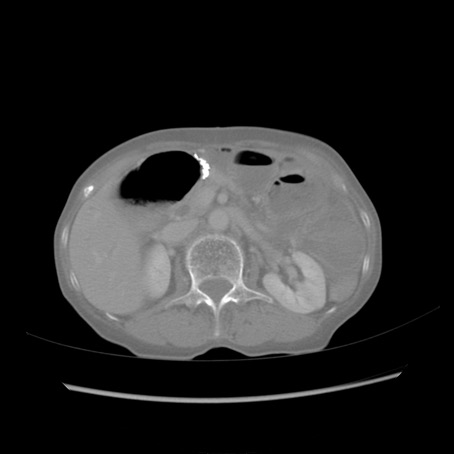

症例25(横断像)

【症例】80歳代女性

【主訴】胸のつかえ感

【現病歴】約9時間前に食後から胸のつかえた感じあり、嘔吐あり、来院。

【既往歴】胃癌(全摘)、胆摘、虫垂炎

【身体所見】心窩部に圧痛あり、反跳痛なし。

【データ】WBC 5700、CRP 0.05